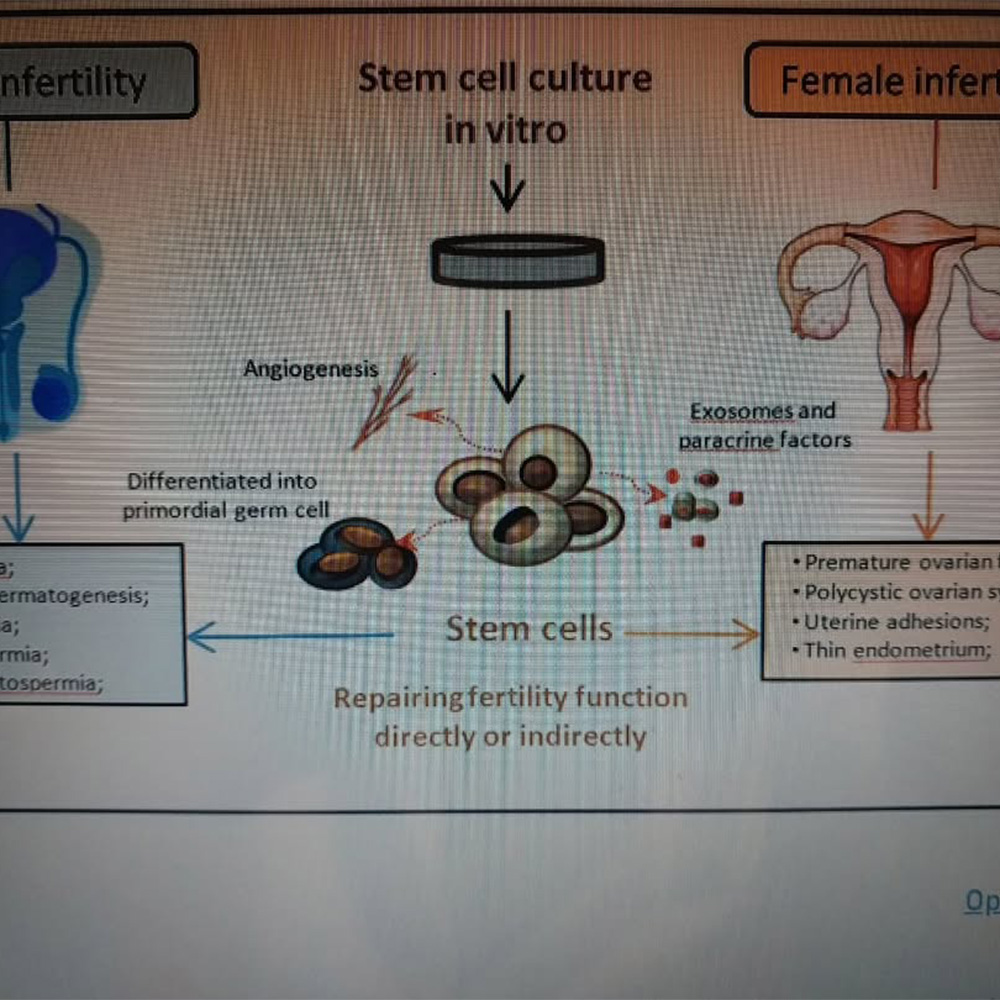

Kısırlıkta Kök Hücre Tedavisi- 1-

Erkekte spermin üretilememesi, spermin az üretilmesi, kadında yumurta yetersizligi veya karın içi rahatsızlıklar, kısırlığa yol açmaktadır. Yardımcı üreme teknikleri bu durumun %50 sini çözmüştür .Erkeklerin...